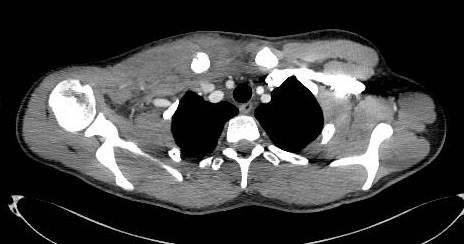

A Contrast CT with 3D CT reconstruction scan (Fig. 2, 3), confirmed the alignment of the floating fragment (rotated and with its medial end pointing posteriorly), which was causing compression on the right Brachiocephalic vein.

Fig. 2: Axial section from Contrast CT Scan showing compression of fracture on brachiocephalic vein